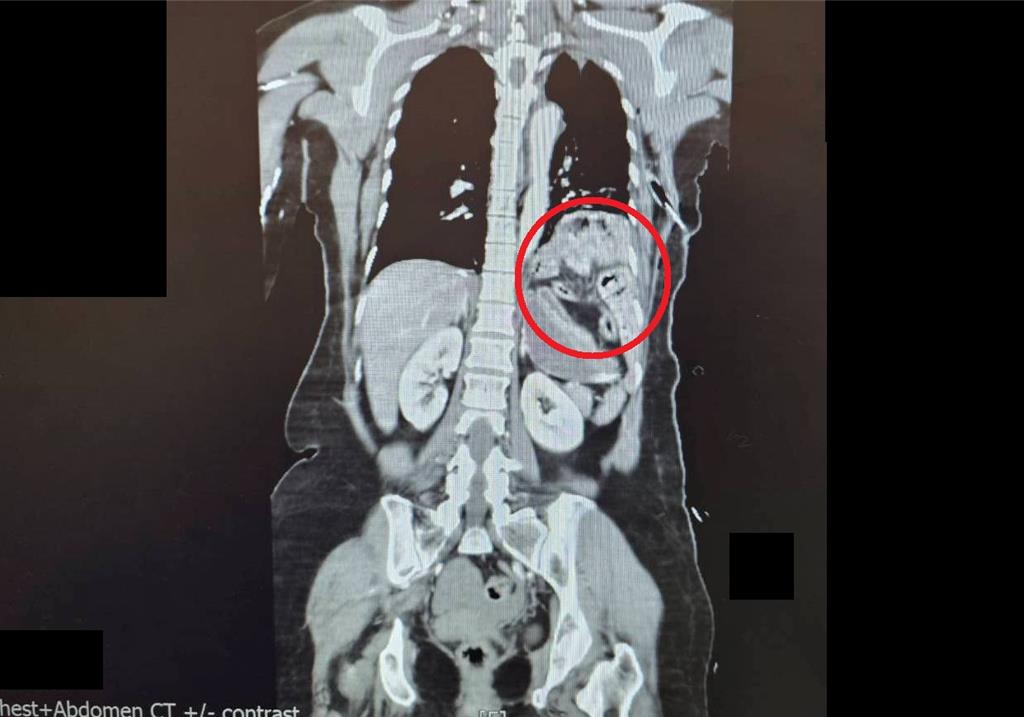

一名58歲陳姓女子因車禍自撞,全身多處重創、生命垂危,送醫後檢查發現其胃部與腸道竟因撞擊力擠入胸腔,胸腹部嚴重受損。外科部主任馮啟彥採用腹腔鏡微創手術,成功修補多處破裂,將傷者從鬼門關前救回。陳姓女子送